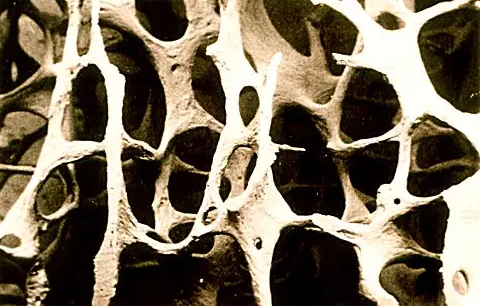

骨质疏松的骨质是这样的

哇!看着挺可怕的赶脚。。